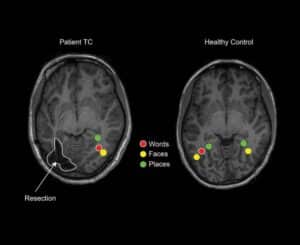

Children can keep full visual perception — the ability to process and understand visual information — after brain surgery for severe epilepsy, according to a study funded by the National Eye Institute (NEI), part of the National Institutes of Health. While brain surgery can halt seizures, it carries significant risks, including an impairment in visual perception. However, a new report by Carnegie Mellon University researchers from a study of children who had undergone epilepsy surgery suggests that the lasting effects on visual perception can be minimal, even among children who lost tissue in the brain’s visual centers.

Normal visual function requires not just information sent from the eye (sight) but also processing in the brain that allows us to understand and act on that information (perception). Signals from the eye are first processed in the early visual cortex, a region at the back of the brain that is necessary for sight. They then travel through other parts of the cerebral cortex, enabling recognition of patterns, faces, objects, scenes, and written words. In adults, even if their sight is still present, injury or removal of even a small area of the brain’s vision-processing centers can lead to dramatic, permanent loss of perception, making them unable to recognize faces, locations, or to read, for example. But in children, who are still developing, this part of the brain appears able to rewire itself, a process known as plasticity.